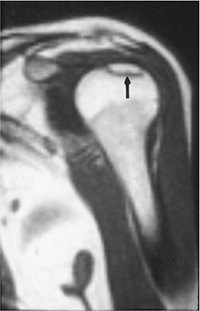

P.507

FIGURE 7-46 T1-weighted coronal image of the shoulder showing a low signal intensity line (arrow) defining the margin of the avascular necrosis.